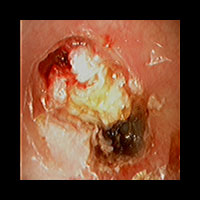

右急性中耳炎(重症) 鼓膜切開

鼓膜が赤く腫れて、鼓膜の奥に白い膿がたまっています。高熱が続き、痛みがとても強かっため、鼓膜切開を行いました。

9日目にほぼ治りました。当院ではできる限り鼓膜切開を行わずに治すことを考えていますが、必要な時はお勧めしています。

初診時 鼓膜切開の直前

初診時 鼓膜切開の直後

9日目